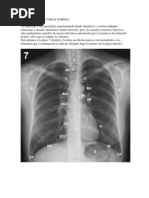

Proyección de órganos en el tórax

Este documento describe la proyección de los órganos del aparato respiratorio sobre la pared torácica. Explica dónde se proyectan los pulmones, lóbulos, segmentos y otras estructuras en las caras anterior, posterior y laterales del tórax. Señala puntos de referencia como la cuarta vértebra torácica y líneas divisorias imaginarias. El documento provee detalles anatómicos precisos sobre la localización de las estructuras respiratorias visibles en la superficie del tórax.

Cara anterior del trax

Un dato de referencia muy til es la cuarta vrtebra

torcica, ya que a este nivel se encuentran proyec

ciones importantes de los rganos profundos, como

la carina principal, punto en el que cambia de de

recha a izquierda el conducto torcico.